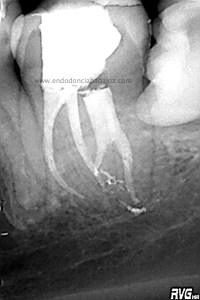

Abrimos el conducto distal con ultrasonidos haciendo la entrada al conducto Disto-Vestivular más recta.

Una vez que conseguimos un buen acceso, con ayuda de Microopeners y ultrasonidos, instrumentamos el conducto y finalmente obturamos todos con sistema de Ola Continua de Buchanan y un backfillin con gutapercha inyectada con Obtura II.